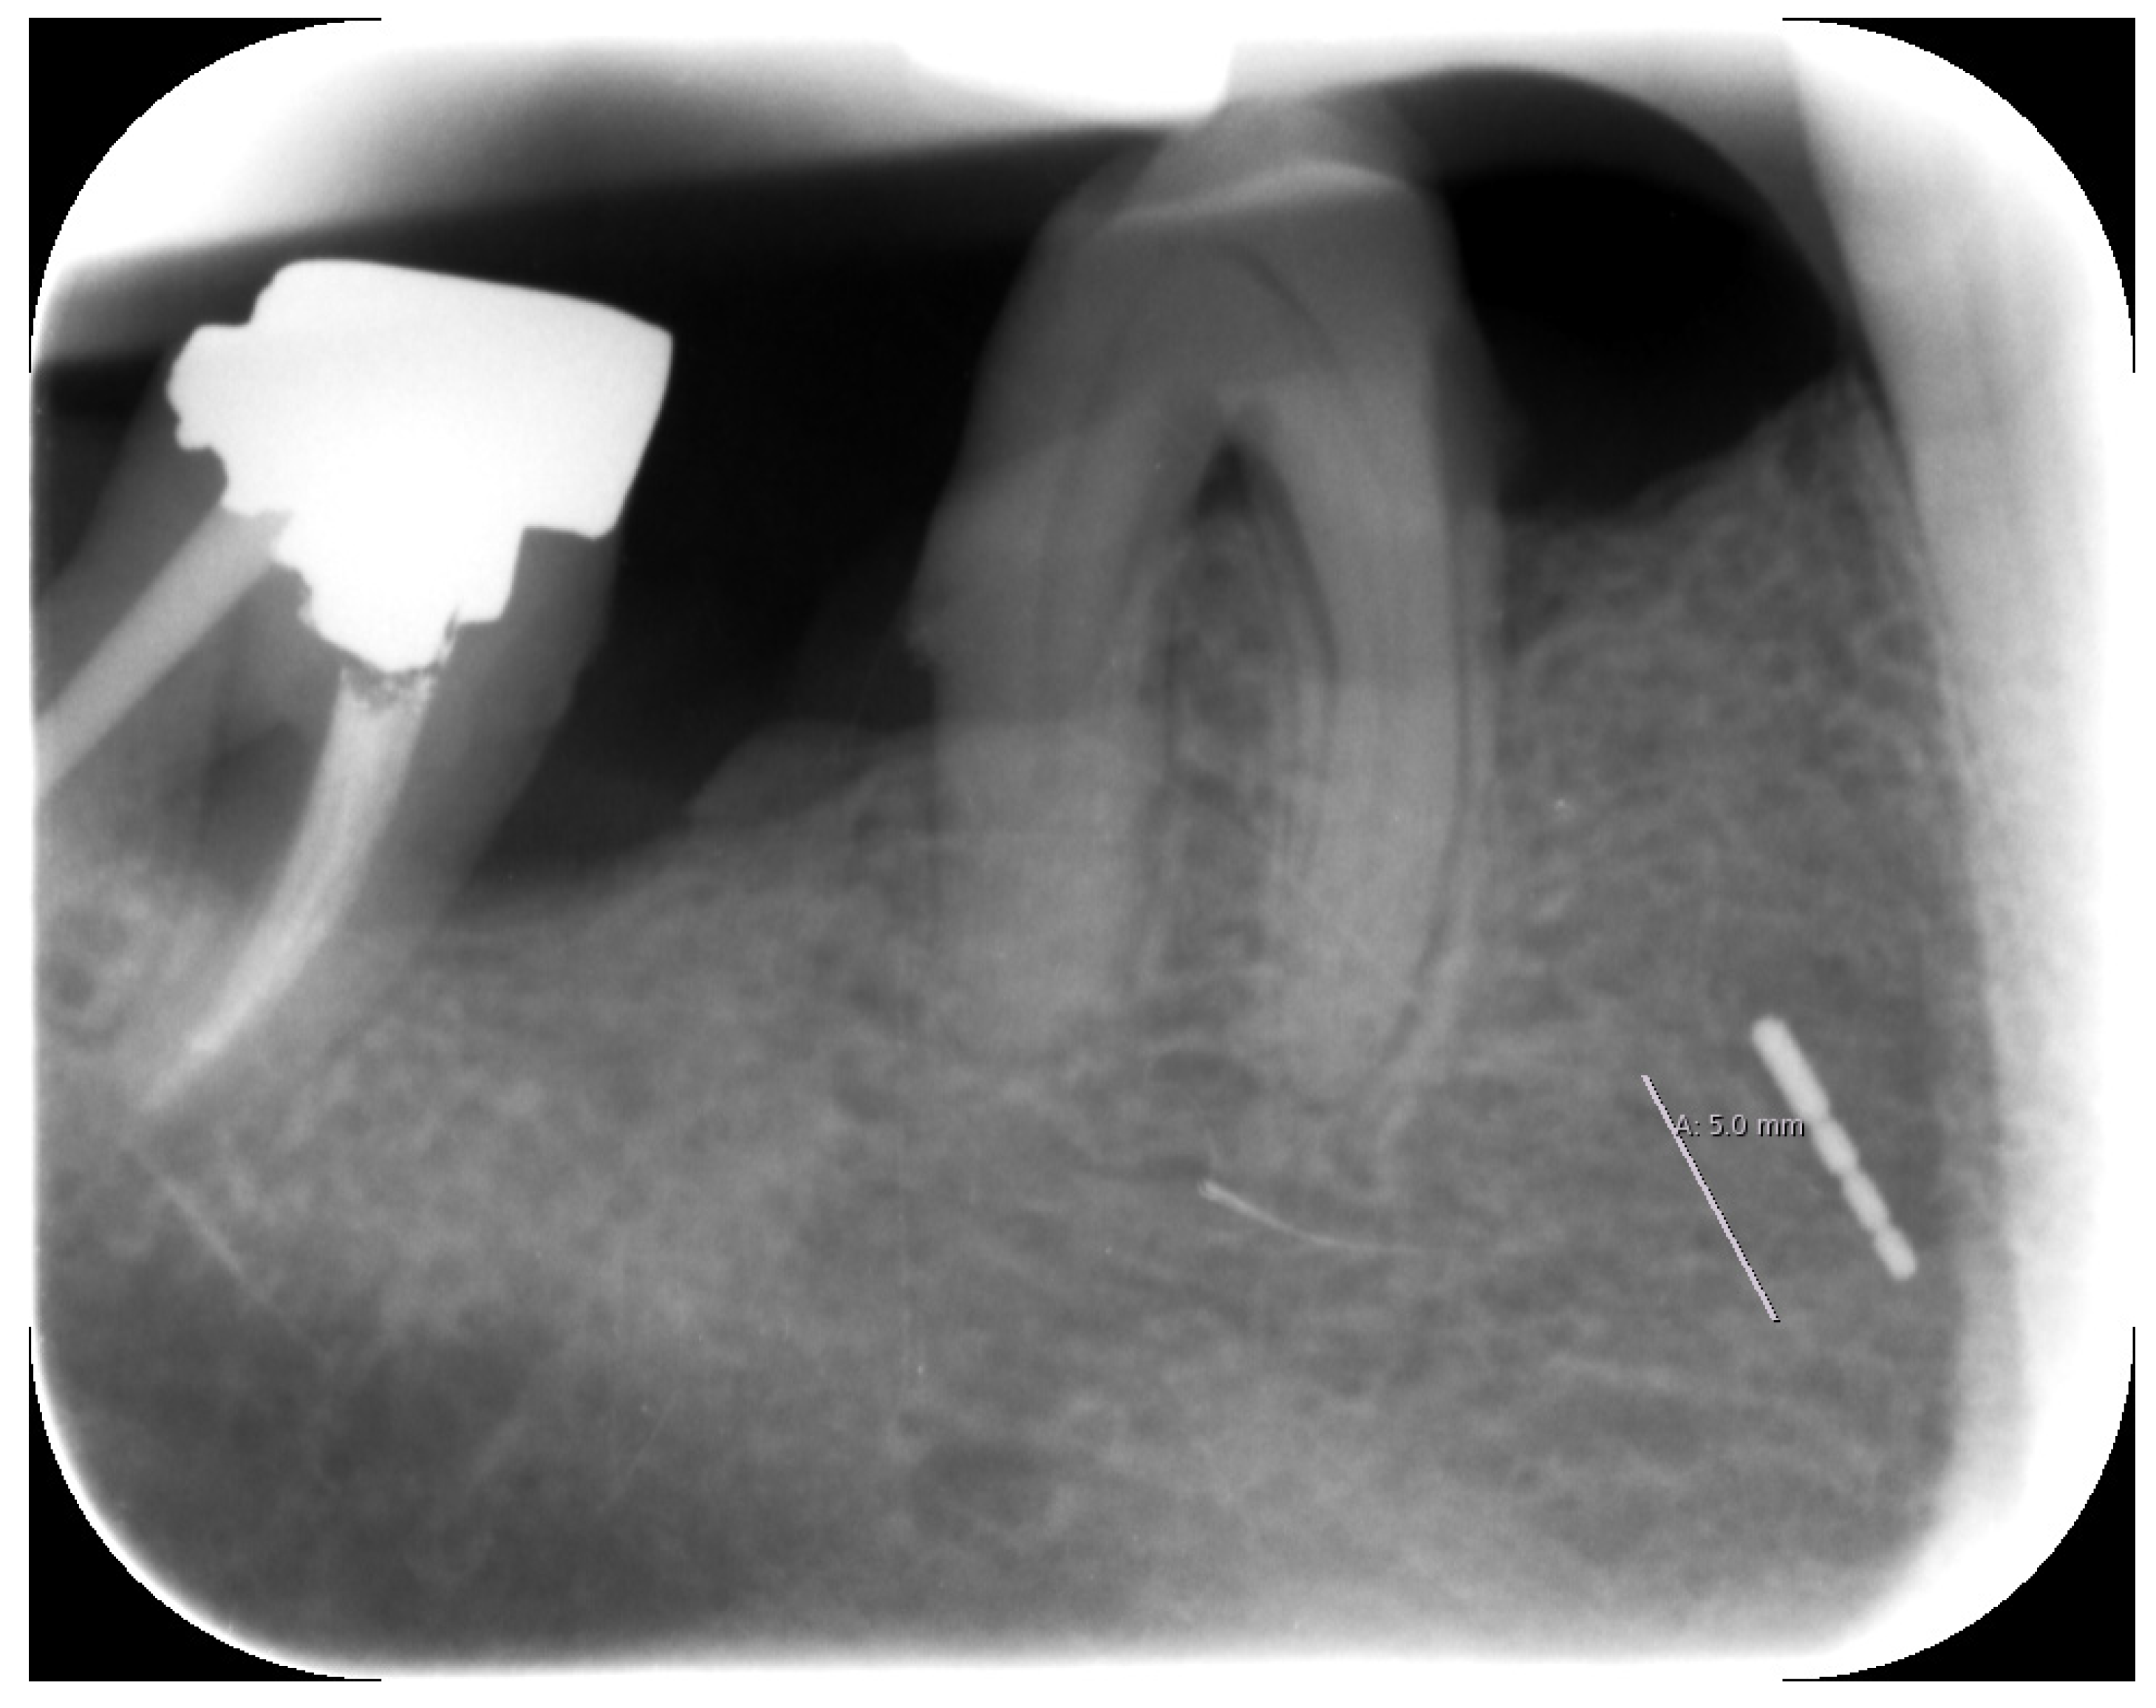

2.3. X-ray

Unfortunately, no older X-rays were available. The single tooth X-ray taken in our clinic in December 2019 clearly identified the broken periodontal probe in two dimensions (Figure 3).

Figure 3.

Periapical X-ray with the broken periodontal probe.

3. Diagnosis

Based on the X-ray findings and visible markings on the metal object, we surmised that this was a broken periodontal probe tip. It appeared to be either a PCPUNC-15 or AE P OWP, both of which are similar, although the latter is shorter and does not have a 4 mm marking (Figure 4). The definitive identification could only be made after removal when we were able to measure and assign the fragment tip accordingly (Figures 5 and 6). Details and photographs of the patient’s oral status can be found in the Supplementary File.